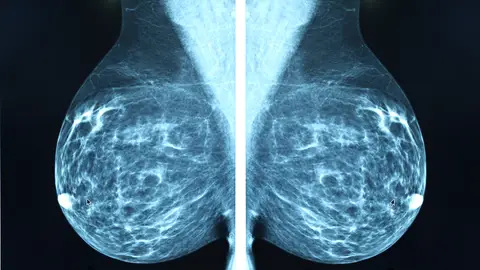

Para llevarlo a cabo, los científicos estudiaron 50 fármacos distintos que inhiben las proteínas quinasas. Y, por sorpresa, una de ellas funcionaba: el ceritinib. "Pudimos demostrar esto no solo en el tubo de ensayo, sino también en cultivos con las llamadas células de cáncer de mama triple negativas", de las más difíciles de tratar.